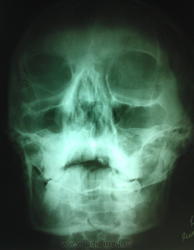

Пол пациента: Мужской пол Тип патологии: Травма Область исследования: Челюстно-лицевая область и шея Методы исследования: Rg Всем добрый вечер, скажите пожалуйста правильно ли я сделал заключение: подвывих С1. Ваше мнение? https://radiomed.ru/sites/default/files/styles/case_slider_image/public/user/18537/wp_000243.jpg?itok=kdHO6XbG ID:31536 Пт, 06/09/2013 - 21:29 #1 И.Бондаренко Не на сайте Был на сайте: 13 часов 29 минут назад Зарегистрирован: 13.09.2011 - 22:55 Публикации: 9213 На основании чего? Сделайте рентгеногрмму через открытый рот, чтобы были видны первые позвонки. Пт, 06/09/2013 - 21:33 #2 Daniel' Не на сайте Был на сайте: 6 месяцев 3 недели назад Зарегистрирован: 27.06.2013 - 22:21 Публикации: 2210 И.Бондаренко wrote: На основании чего? Сделайте рентгеногрмму через открытый рот, чтобы были видны первые позвонки. если приглядеться то можно увидеть и боковые массы атланта и зуб аксиса. второй снимок как раз с открытым ртом. Пт, 06/09/2013 - 21:47 #3 И.Бондаренко Не на сайте Был на сайте: 13 часов 29 минут назад Зарегистрирован: 13.09.2011 - 22:55 Публикации: 9213 Это не то. Просто попытка. Надо переделать. Пт, 06/09/2013 - 22:01 #4 Андрей Юрьевич Не на сайте Был на сайте: 2 недели 2 дня назад Зарегистрирован: 16.11.2008 - 22:16 Публикации: 18106 Подвывиха С1 без кривошеи не бывает. Мы это обсуждали, когда-то http://www.radiomed.ru/cases/podvyvikh-s-3 Андрей Юрьевич Втр, 17/09/2013 - 09:05 #5 ЕЕЮ Не на сайте Был на сайте: 2 года 6 месяцев назад Зарегистрирован: 26.08.2013 - 11:22 Публикации: 410 Я не вижу С1

На основании чего? Сделайте рентгеногрмму через открытый рот, чтобы были видны первые позвонки.

Подвывиха С1 без кривошеи не бывает. Мы это обсуждали, когда-то http://www.radiomed.ru/cases/podvyvikh-s-3

Я не вижу С1